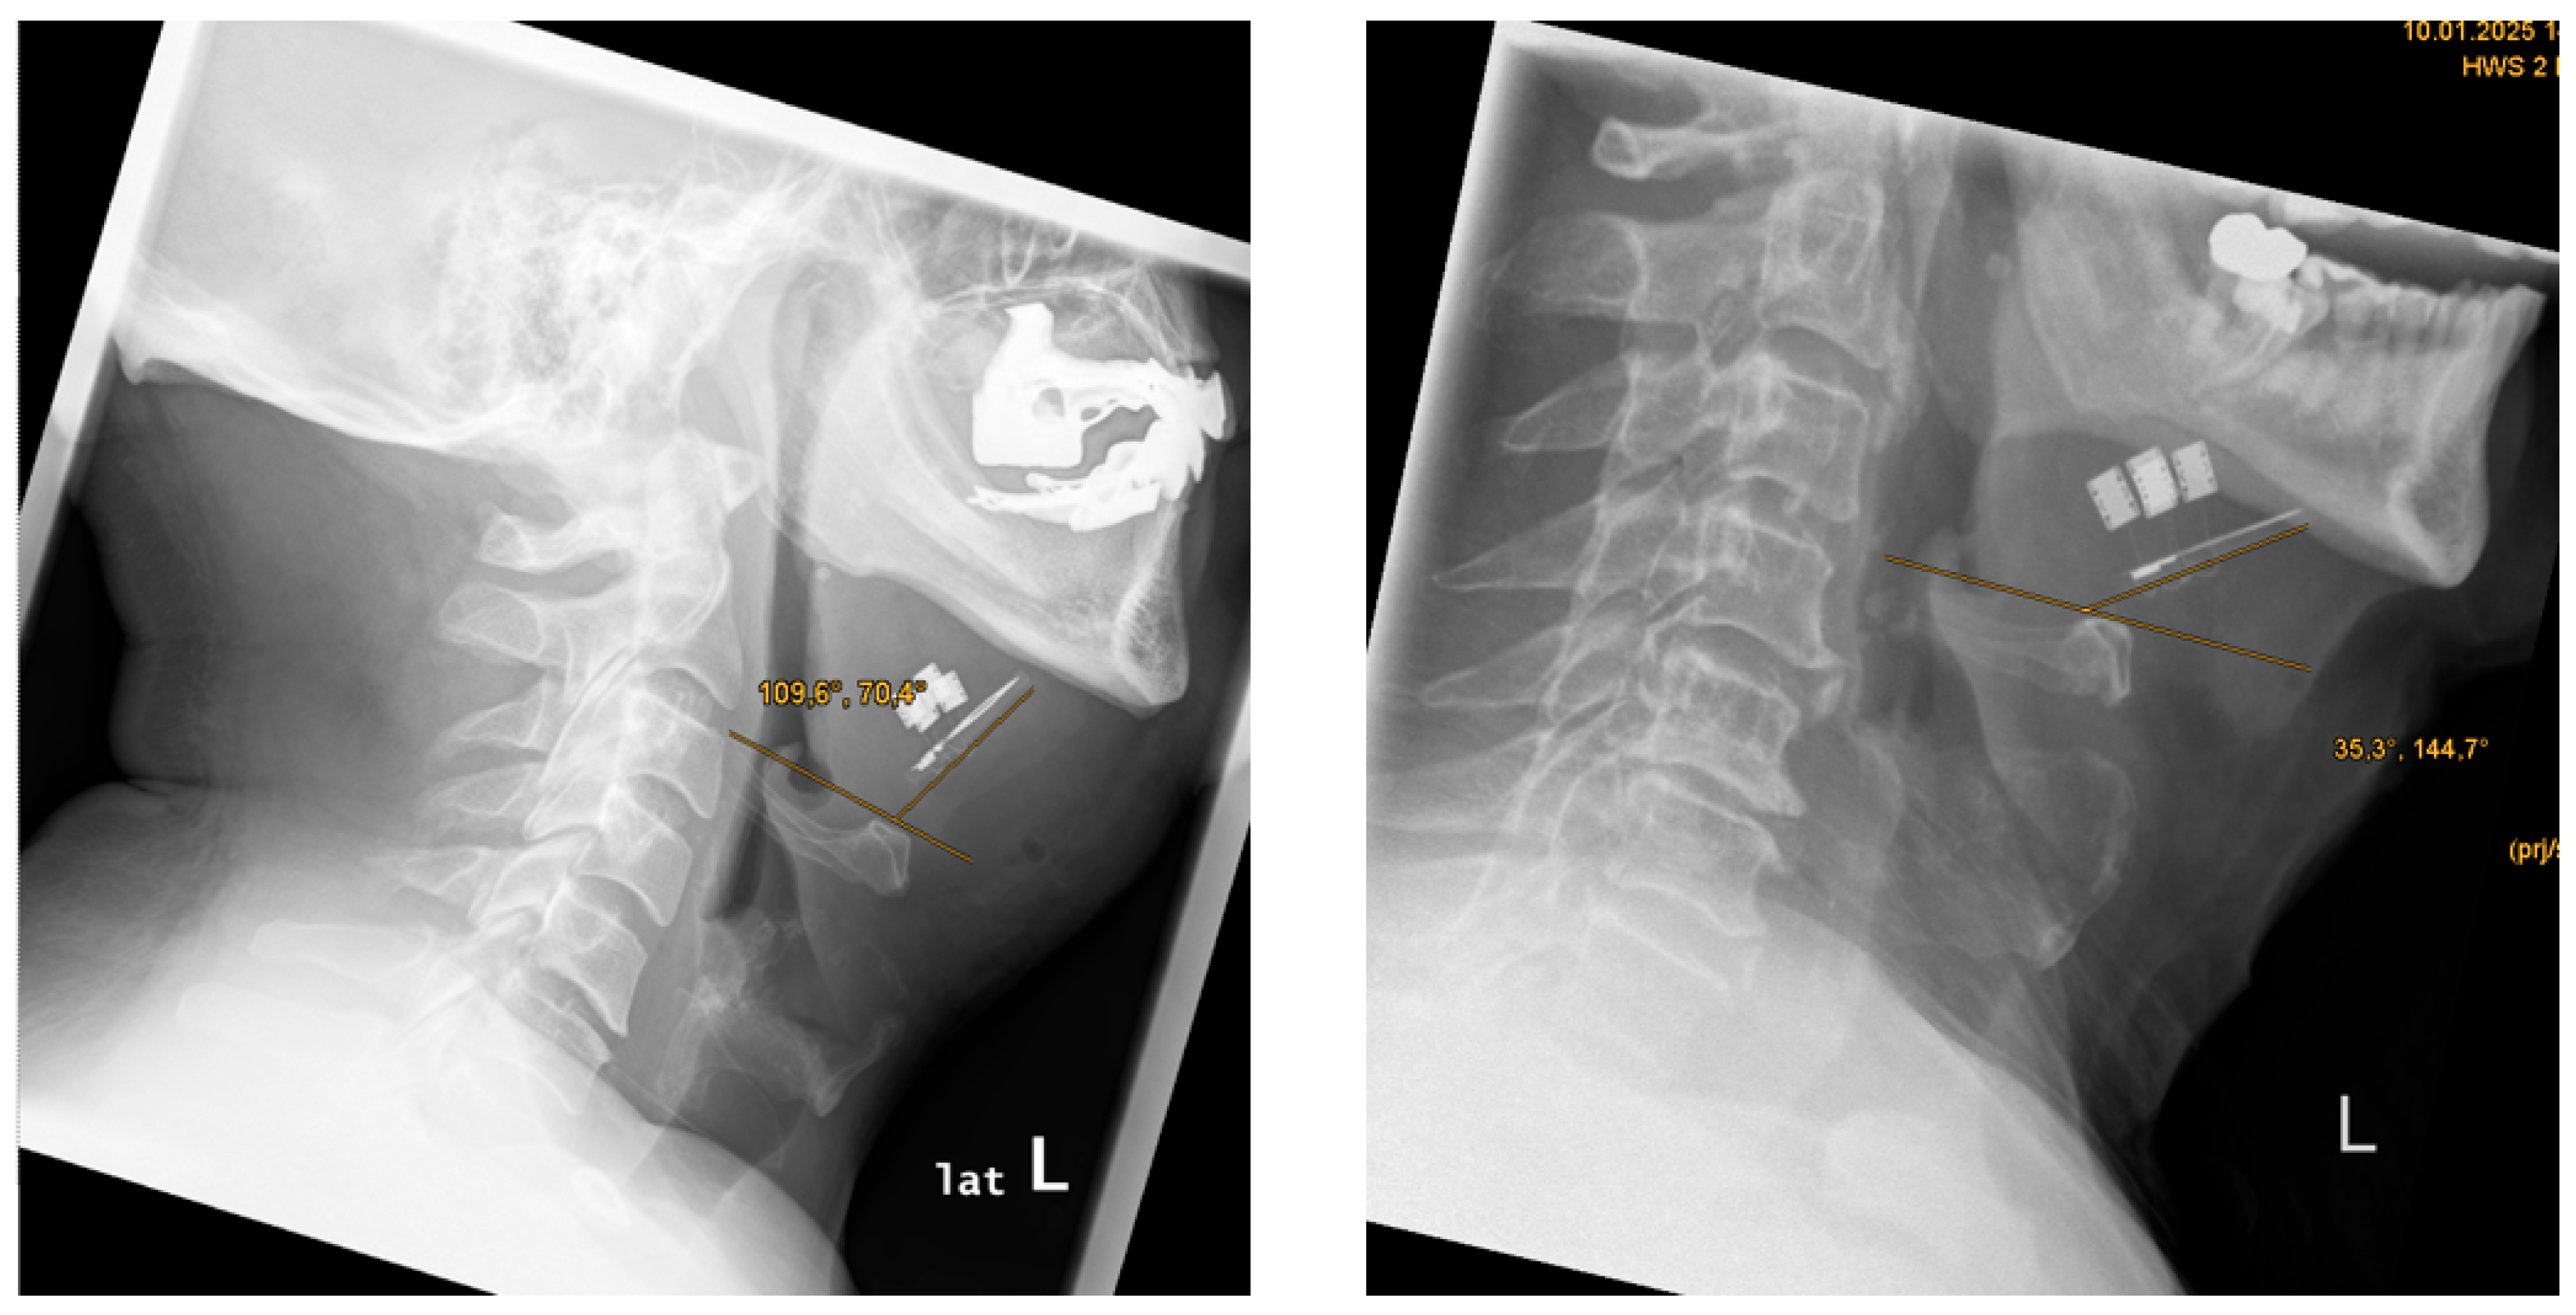

| 5 | 37 | 32 | yes | yes | yes | strong | no | yes | 93,2 | 23,9 | 54,5 | 15,4 | 13,9 | 16,9 | -3,0 | asymmetry | 35,3 | proximal | proximal |

| 3 | 51 | 28 | yes | no | n/a | n/a | no | yes | 109,3 | 32,6 | 48,4 | 17,2 | 15,0 | 19,3 | -4,3 | asymmetry | 60,3 | proximal | proximal |